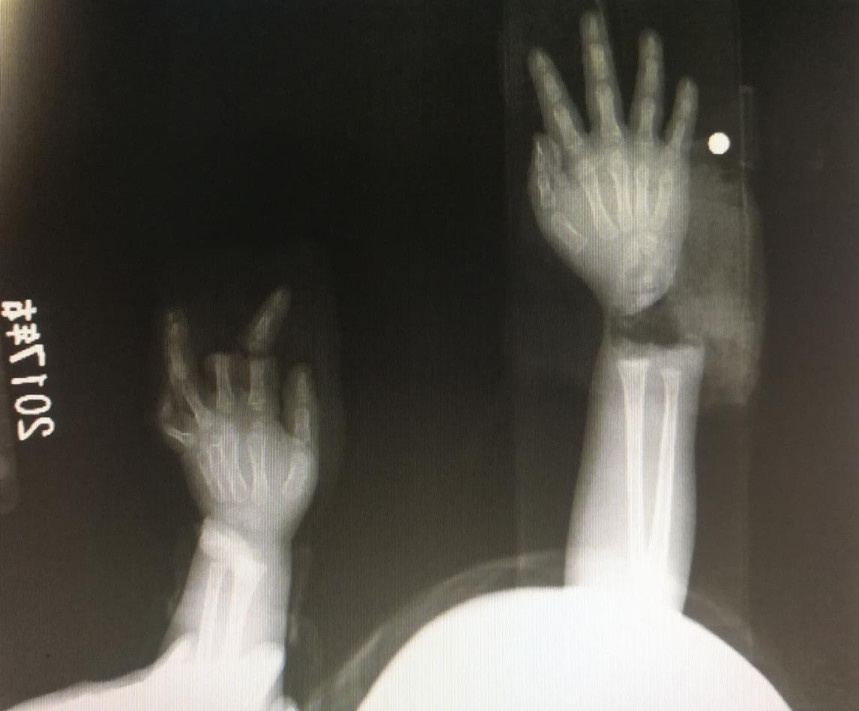

“急診在哪,急診在哪”,伴隨著一聲聲急促的問詢,一位年輕女士抱著渾身是血的小孩疾步前往急診室,懷里的小孩在疲憊與疼痛的交織下,時睡時醒。鑒于小孩的情況,急診醫(yī)生迅速安排給小孩拍了X光片,影像片結(jié)果顯示小孩左手手腕完全離斷,右手中、食指離斷,距離事發(fā)時間已經(jīng)3個多小時,需盡快安排手術(shù)。

經(jīng)過長達(dá)5個多小時的手術(shù),小宇(化名)終于被送出了手術(shù)室,離斷的手腕和手指均已完成再植,但關(guān)于斷指的存活與否還需要經(jīng)過一個十天的觀察期。小宇的主治醫(yī)生是長沙年輪骨科醫(yī)院手足外科馬思成醫(yī)生,據(jù)馬醫(yī)生介紹,小宇受傷情況比較嚴(yán)重,失血過多,而且兩個手都存在完全離斷的情況,手術(shù)時安排了兩組醫(yī)生同時進(jìn)行,整個手術(shù)過程比較順利,目前小宇還處于觀察期。